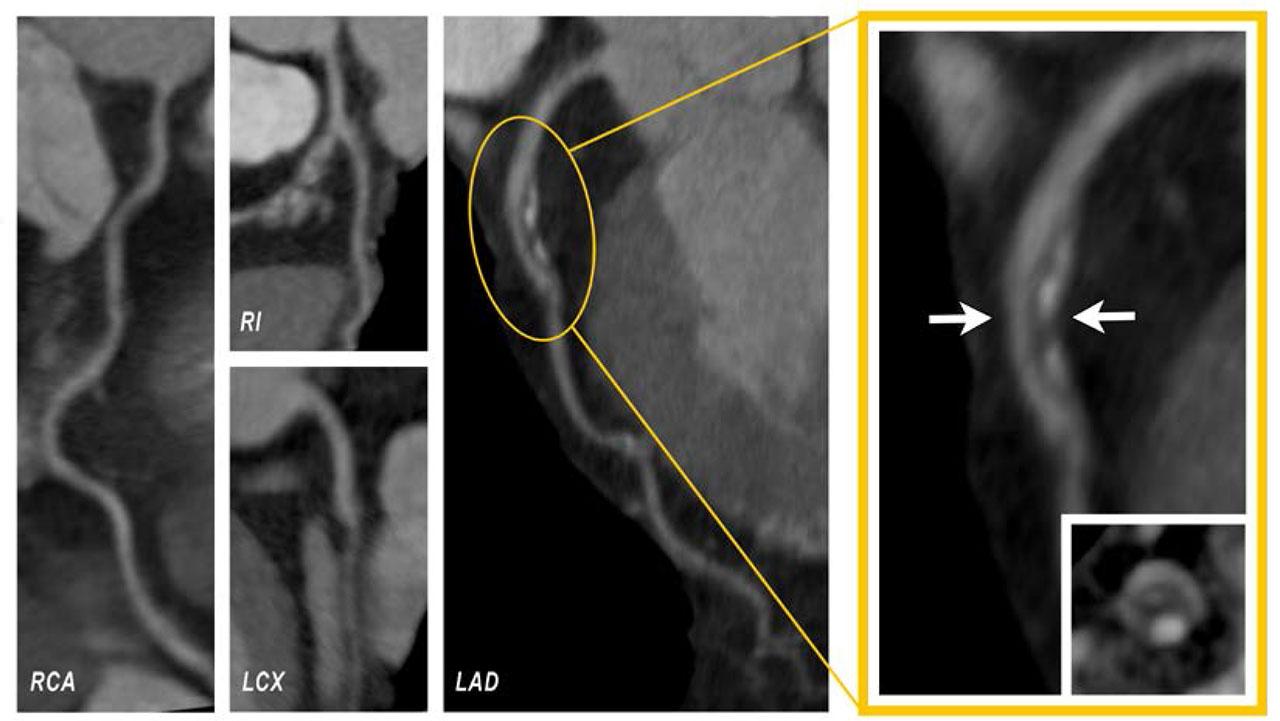

Based on her symptoms and test outcomes, we decided to conduct a contrast-enhanced CCTA using a 128-slice scanner (Somatom Definition AS, Siemens, Erlangen). The procedure commenced with a coronary artery calcium (CAC) scan. This was followed by the administration of an iodine-based contrast fluid, dosed according to the patient's body weight. The patient's CAC score was determined to be relatively low at 26.7. The CCTA revealed a notable 70% stenosis in the proximal portion of the left anterior descending artery (LAD), caused by a mixed plaque exhibiting signs of vulnerability. These signs included positive remodeling, a low-density atheroma, and a distinct napkin-ring sign, as highlighted in Figure 1 with a yellow frame.

CCTA reveals severe stenosis in the proximal LAD (white arrows), caused by a mixed plaque, which showed clear signs of vulnerability: positive remodeling, low-attenuation plaque, and the napkin-ring sign.